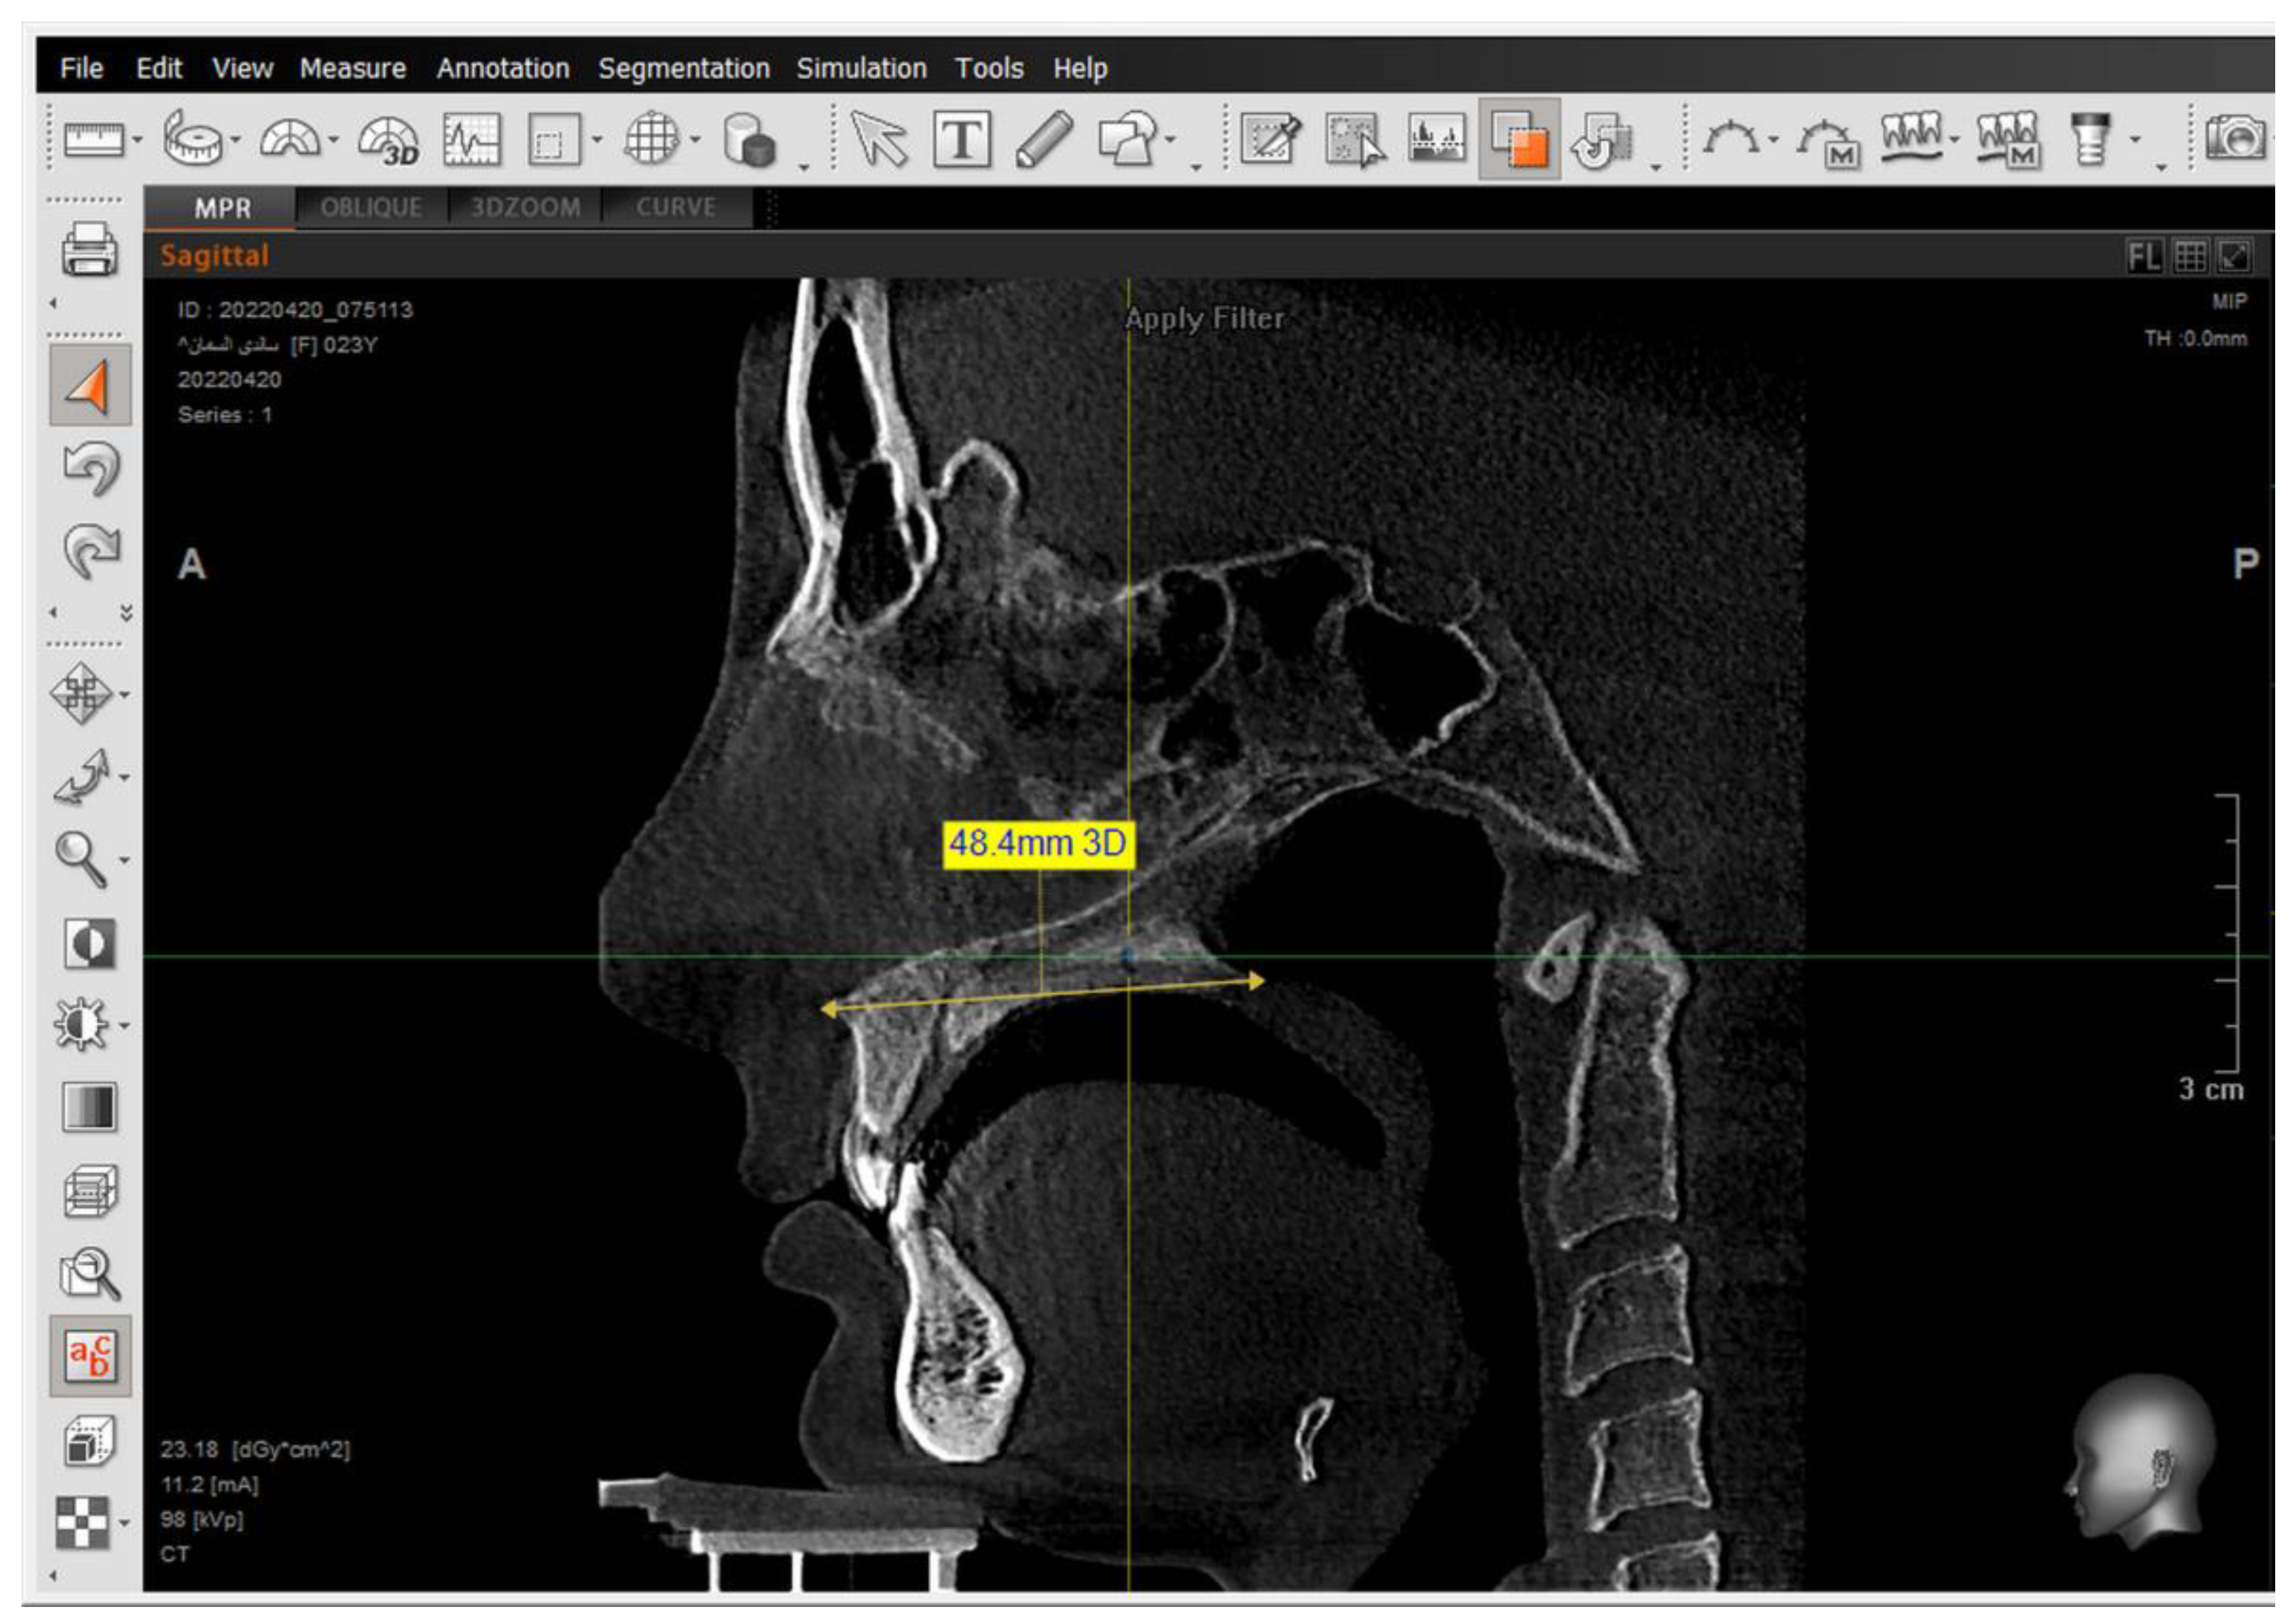

A 2D-Unsharpen filter was chosen after opening the radiograph to control the clearance of bone borders. The planes that were used and drawn were (ANS-PNS) (Go-Me) in the sagittal view, and (J-J) (Ag-Ag) in the frontal view. The green and yellow (axial and coronal plane) were moved to pass through the axis of the tooth (Figure 2 and Figure 3). Then, the orange sagittal plane in the coronal window was moved until it reached the middle of the incisal margin and the apex of the root (Figure 4). Thus, the largest buccal–lingual section of the centrals and canines was obtained in the sagittal view, referring to the buccal alveolar bone crest, detecting any bony defects (Figure 3). The definition of an alveolar defect when the cortical bone is around the vestibular surface of the root refers to the absence of at least three sequential sagittal views [8]. The defect was confirmed by 3D Zoom when the 2D reading was not clear (Figure 5) [32].

Next, a reset to the MPR (Multi-Planar Reconstruction) was performed to measure the distance between the jaw plane and the referred alveolar bone crest (Figure 6) [32].

The same steps were performed for the 2nd premolars but in different directions—in the coronal window for referring buccal alveolar ridge and dehiscence and fenestrations, and in the sagittal window for determining the tooth axis.

The presence of the dehiscence and fenestrations (Figure 5), and the distance between the buccal alveolar crest perpendicular to the reference jaw plane for centrals and canines in the sagittal view were measured (Figure 6), as well as the 2nd premolars in the coronal view in maxilla and mandible (Figure 7) at T0 and T2.

Figure 6. Measuring the distance between the tip of the buccal alveolar bone crest and the maxillary plane, and measuring the angle formed between the tooth longitudinal axis and the maxillary plane in the sagittal view.

Figure 7. Setting the tip of the alveolar bone crest. Then, measuring the distance between the tip of the buccal alveolar bone crest and the maxillary plane.